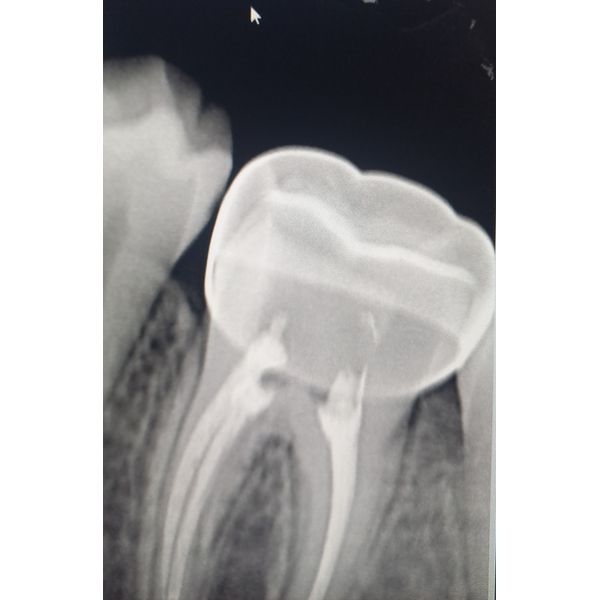

Затем обработали оставшуюся полость зуба, изолировали устья корневых каналов, обработали зуб под стандартную стальную коронку, сняли коффердам и примерили коронку. На рентгенограмме было видно, что коронка прилегает герметично до анатомической шейки зуба. Поэтому коронку сняли, обработали и затем зафиксировали.

После полного исчезновения симптомов девочка жуёт нормально, ткани зуба полностью восстановлены металлической коронкой, которую нужно носить до полного формирования прикуса.